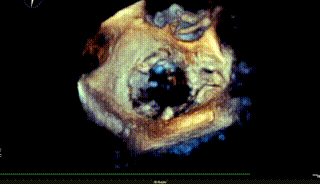

在MultiVue下定位与夹合

该患者为原发性二尖瓣反流患者,病变位置偏P3+PC。目前国内外专家对该类非典型病例患者的TEER治疗尚刚刚起步。由于非2区病变患者瓣膜反流位置较偏,操作器械系统输送到达目标位置困难、同时长轴切面与实际夹臂存在夹角,需要使用具有MultiVue(三维重建)功能的超声机器,且手术中缠绕腱索的风险增大,该类患者往往在筛选期就被拒绝难以得有救治,而ValveClamp系统通过心尖操作,选取最佳穿刺点,仅40分钟就植入1枚夹子,术后几乎无反流,充分显示器械操作便利性、高效性。该例手术的成功,标志着河南省二尖瓣反流经导管介入治疗方面取得新突破,该技术未来将造福更多省内二尖瓣反流患者。